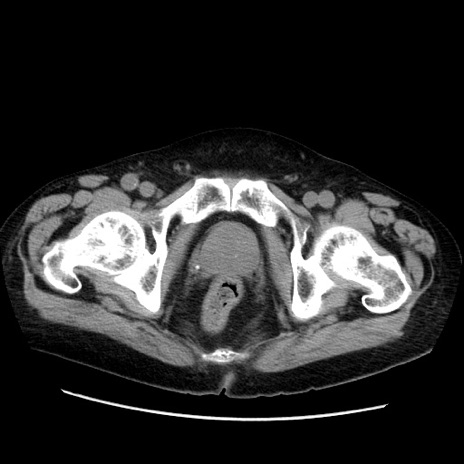

症例21(横断像)

【症例】70歳代男性

【主訴】腹痛

【現病歴】肝硬変・肝細胞癌にてかかりつけの方。約9時間前に食後より腹痛出現。症状が徐々に増悪し、嘔吐出現したため来院。

【既往歴】肝硬変、肝細胞癌(RFA、TACE後)

【身体所見】意識清明、表情苦悶様、BT 36℃、BP 129/78mmHg、P 88bpm、SpO2 97%(RA)、右上腹部から心窩部にかけて圧痛あり、反跳痛なし、筋性防御あり。

【データ】WBC 5800、CRP 0.16